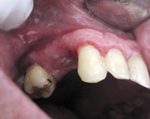

W badaniu klinicznym stwierdzono obfite złogi kamienia nazębnego, świadczące o niedostatecznej higienie jamy ustnej. Guz o średnicy 20 mm wyrastał z dziąsła między zębami 13 a 16 i obejmował wyrostek zębodołowy zarówno od strony przedsionkowej, jak i podniebiennej. Miał nieregularny kształt, kolor jasnoróżowy, umocowany był na szerokiej szypule i częściowo od strony podniebiennej pokryty włóknikowym nalotem (ryc. 1).